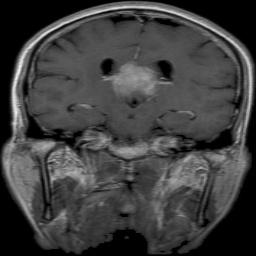

The dataset used in this project is the Brain Tumor Classification (MRI). It consists of MRI scans categorized into four classes: 👇

Glioma Tumor | Meningioma Tumor |

Normal | Pituitary Tumor |

![]() Actual: Glioma Tumor Predicted: Glioma Tumor (Confidence: 1.00) | ![]() Actual: Glioma Tumor Predicted: Glioma Tumor (Confidence: 1.00) |

![]() Actual: Meningioma Tumor Predicted: Meningioma Tumor (Confidence: 1.00) | ![]() Actual: Meningioma Tumor Predicted: Meningioma Tumor (Confidence: 0.81) |

![]() Actual: Normal Predicted: Normal (Confidence: 0.98) | ![]() Actual: Pituitary Tumor Predicted: Pituitary Tumor (Confidence: 0.99) |

![]() Actual: Pituitary Tumor Predicted: Pituitary Tumor (Confidence: 0.51) | ![]() Actual: Pituitary Tumor Predicted: Meningioma Tumor (Confidence: 0.43) |